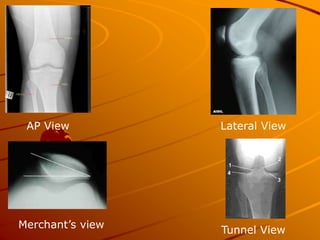

What Radiographs to Order

Most Patients 3 views

– AP

– Lateral

– Merchants

Teenagers with chronic knee pain

and recurrent effusion

– Add Tunnel View (PA with knee flexed

40-50 degrees)

Loooks for osteochondritis dissecans on

Femoral Condyles)

AP View Lateral View

Merchant’s view

Tunnel View